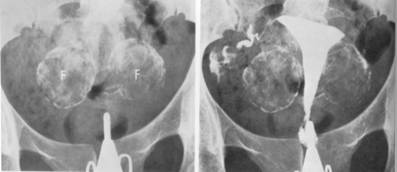

RADIOGRAFIA SIMPLA evidentiaza modificarile de forma si dimensiuni ale oaselor bazinului, secundare unor procese patologice ale organelor genitale feminine sau a unor malformatii. Calcificarile sunt frecvente in fibroamele uterine, TBC, mai rar in tumorile maligne. Radiopelvimetria permite masurarea diametrelor bazinului osos si a diametrelor fetale pentru stabilirea raportului dintre bazinul obstretical si craniul fetal.

Fig. 378 Leifibromioame uterine calcificate